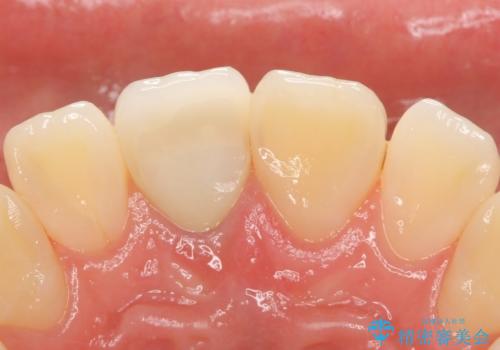

- 右上1番目の前歯の変色が気になるといらっしゃった方の症例です。

再根管治療後、オールセラミッククラウンによる補綴を行いました。

今回用いたオールセラミッククラウンはジルコニアフレームという白い素材の上にセラミックを盛っているため、審美性が非常に高いのが特徴です。

また、ジルコニアは人工ダイヤモンドの材料にも使われているほど高い強度を持っており、そのためオールセラミッククラウンは審美性だけでなく、奥歯やブリッジの補綴も可能とするクラウンです。